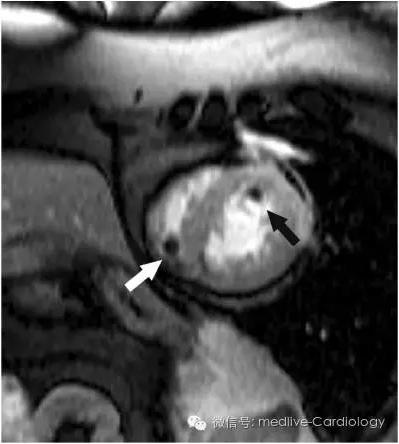

左室或右室壁无运动为血栓形成提供了基础(图3)。与冠状动脉闭塞引起的急性心肌梗死导致的血栓不同,TTC患者的血栓是多发的,且位置分布不同。这些血栓可以引起体循环或肺循环栓塞。因此,除大出血外,对TTC患者初期静脉应用肝素是合理的。就作者个人经验来说,TTC出现心室内血栓时,通常会在心室功能恢复正常前持续应用华法林。

图3 心脏MRI提示右室和左室血栓形成(白色箭头示右室、黑色箭头示左室)。